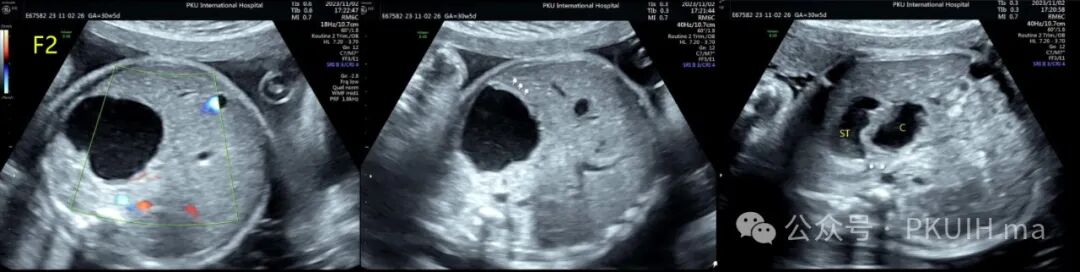

上图是一个单绒双羊双胎在孕30周发现胎儿胃旁囊性肿物,观察中可见大小有变化,同时可见胃壁结构,考虑胃重复畸形